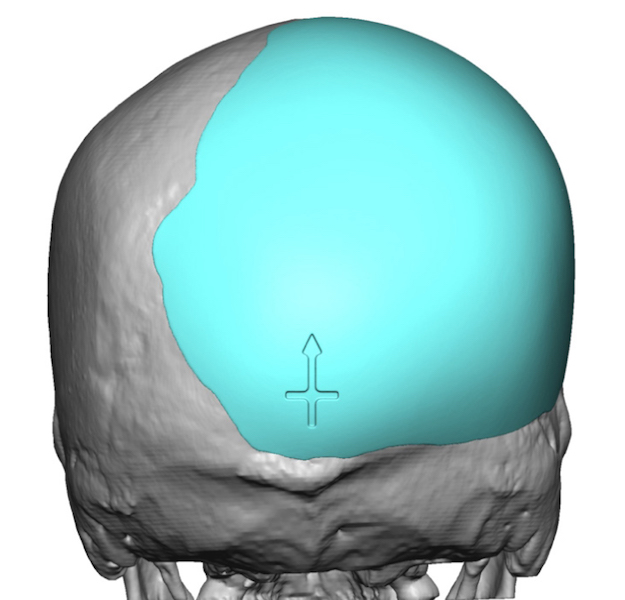

Desire to build up the flatter upper part of the back of his head.

Upper occipital skull augmentation using a custom skull implant.

Desire to build up the flatter upper part of the back of his head.

Upper occipital skull augmentation using a custom skull implant.